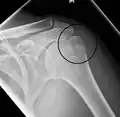

A fracture of the greater tuberosity as seen on AP X ray -

A fracture of the greater tuberosity of the humerus -